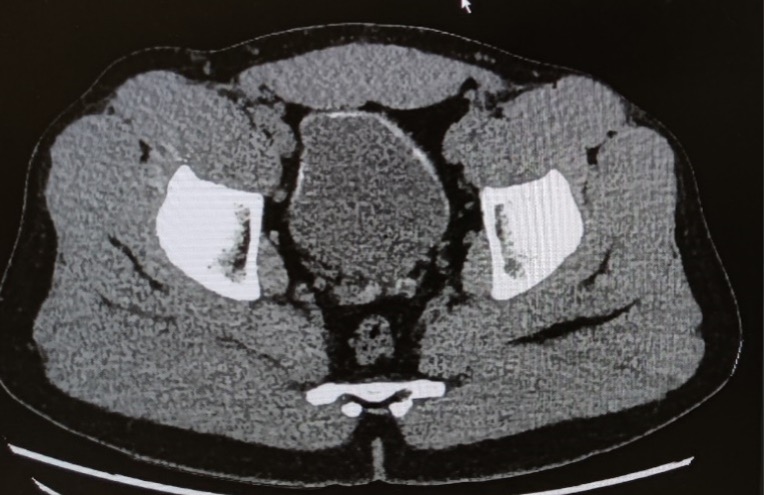

Tu regardes les images immédiatement avec la chirurgienne, qui te confirme la présence d’un diverticule enflammé correspondant à une diverticulite Hinchey Ia. Dans l’attente des suites à donner à ce diagnostic de diverticulite, tu vois également cette image au niveau de la vessie :

Quelle suite de prise en charge organises-tu ?